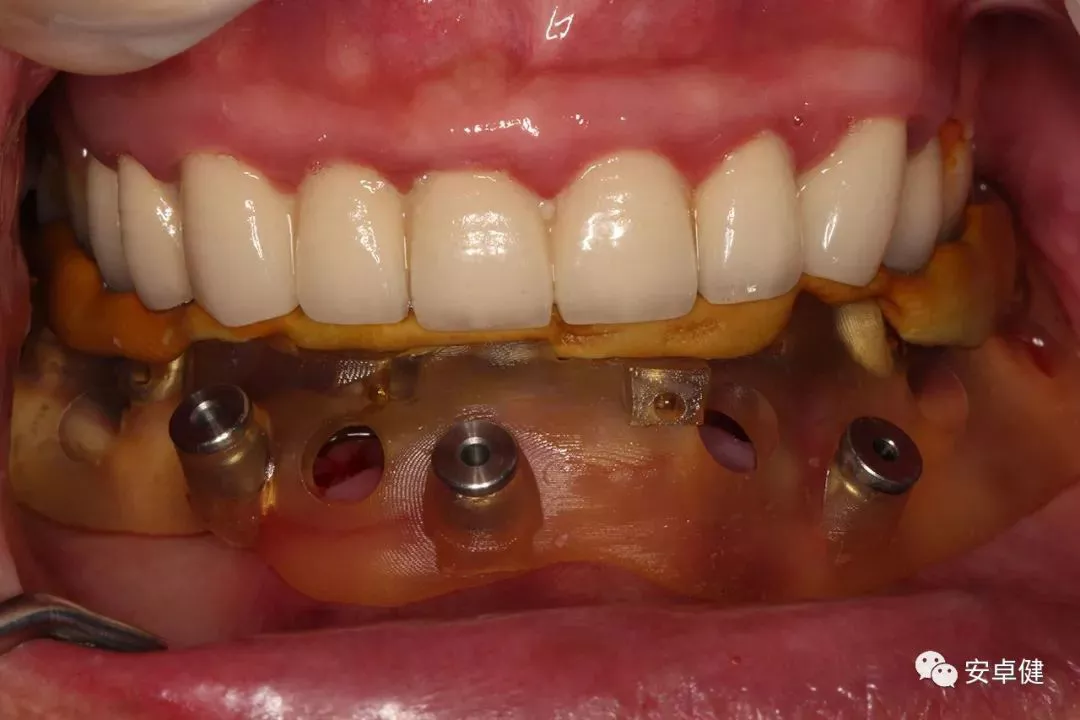

▷ 永久修复

患者术后16个月:

• 于口内试戴原厂纯钛切削一体式桥架,并检查前牙排蜡外形及后牙咬合关系;

• 聚合瓷烤塑制作最终修复体;

• 为减少牙面磨耗,于后牙区制作360度防裂纯钛金属带;

• 试戴满意后,二级螺丝加力至15N;

• 特氟龙封闭螺丝孔,光固化复合树脂封闭上方螺丝通道,完成最终固定式种植义齿修复;